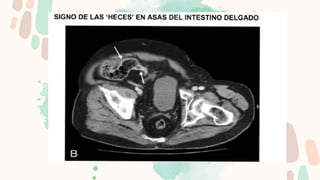

Los puntos más importantes son detectar el punto de transición, determinar la causa y

descartar la presencia de complicaciones.

Para facilitar la búsqueda del PT se emplean dos signos:

El “signo del pico”, dado que el punto de cambio de calibre simula un pico.

El “signo de las heces”, dado que debido a la obstrucción en el PT las heces se acumulan

proximalmente a este dando la típica imagen de patrón en miga de pan.